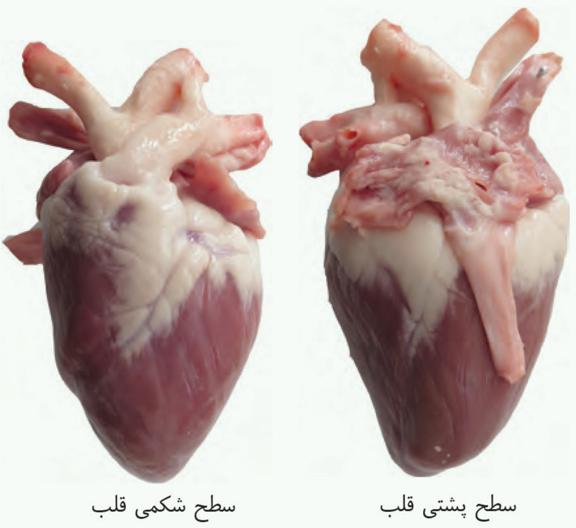

در برش طولی کلیه، سه بخش مشخص دیده میشود که از بیرون به درون عبارتاند از بخش قشری، بخش مرکزی و لگنچه.

در بخش مرکزی، تعدادی ساختار هرمی شکل دیده میشود که هرمهای کلیه نام دارند. قاعده هرمها به سمت بخش قشری و راس آنها به سمت لگنچه است. هر هرم و ناحیه قشری مربوط به آن را، یک لَپ کلیه مینامند.

لگنچه، ساختاری شبیه به قیف دارد. ادرار تولید شده، به آن وارد و به میزنای هدایت میشود تا کلیه را ترک کند.

تشریح کلیه گوسفند

بخش قشری کلیه از بخش مرکزی تیرهتر است.

در ناف کلیه چربی وجود دارد.